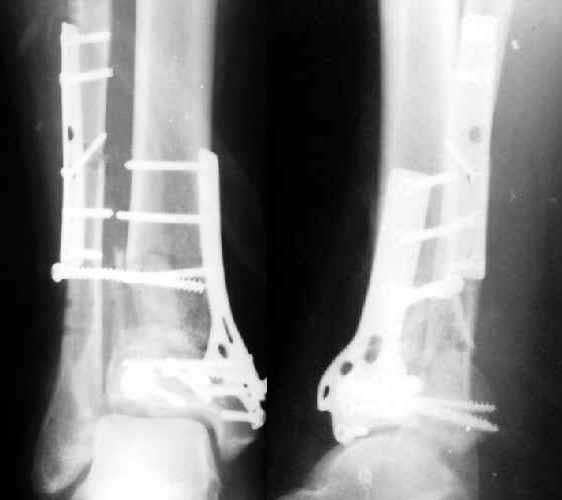

6 weeks ago a pilon fracture in a male 45 years old was ORIFed (image 1). The patient also had the opposite foot injured. Due to urological problems he then was transferred to another facility. Against our advice he walked with partial weight-bearing. Partial loss of fixation was revealed when a month later he visited our unit (image 2).

This is a BIG problem, that fortunately is somewhat less common now than 10 years ago. The fibula and a large piece of distal lateral tibia are now displaced laterally about 1 cm. It is difficult to assess how well reduced the tibia articular surface was and is. You might consider:

3. What is the status of the fixation? Is it solid or grossly loose? This appears somewhere in between with perhaps syndesmosis instability but the other fixation (fibula, tibia articular surface, tibia meta-diaphysis ?OK)

4. What is the status of the reduction. Again, syndesmosis very wide but other (fibular length, tibia articular surface, tibia alignment, talus beneath plafond) seems OK.